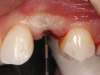

(56.) The provisional restoration was delivered and tightened to 15 Ncm while applying counter torque. Note that there is no pressure on the surrounding tissues and that the gingival embrasures were left open to allow for maximum incisal migration of the gingiva and papillae. The palatal and incisal surfaces were evaluated and modified to ensure that there was no contact throughout the excursive range.

Figure 56

(57.) The provisional restoration was delivered and tightened to 15 Ncm while applying counter torque. Note that there is no pressure on the surrounding tissues and that the gingival embrasures were left open to allow for maximum incisal migration of the gingiva and papillae. The palatal and incisal surfaces were evaluated and modified to ensure that there was no contact throughout the excursive range.

Figure 57